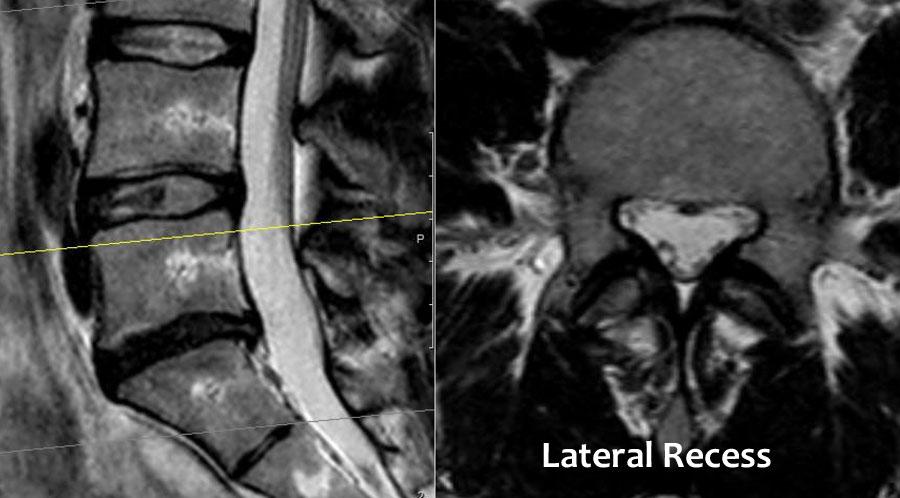

Chủ yếu do thoát vị đĩa đệm và ít thường gặp hơn do hẹp ống sống. - Mức độ ngách bên.

Đây là vùng nằm phía dưới đĩa đệm, nơi rễ thần kinh đi theo hướng bên hơn về phía lỗ liên hợp.

Hẹp ngách bên được gây ra bởi thoái hóa khớp mỏm khớp, thường kết hợp với phì đại dây chằng vàng và phồng đĩa đệm. - Lỗ liên hợp.

Cuộn qua các hình ảnh để quan sát đường đi của các rễ thần kinh tại mức độ đĩa đệm, ngách bên, lỗ liên hợp và ngoài lỗ liên hợp.

Tại mỗi mức độ có thể thấy các bệnh lý đặc trưng, nhưng có sự chồng lấp đáng kể.

Ở bệnh nhân thoái hóa khớp mỏm khớp, các gai xương có thể phát triển vào trong và làm hẹp ngách bên, hoặc phát triển lên trên và làm hẹp lỗ liên hợp.

Khi thoái hóa khớp mỏm khớp nặng xảy ra hai bên, có thể gây hẹp ống sống và chèn ép tất cả các rễ thần kinh tại tầng đó.